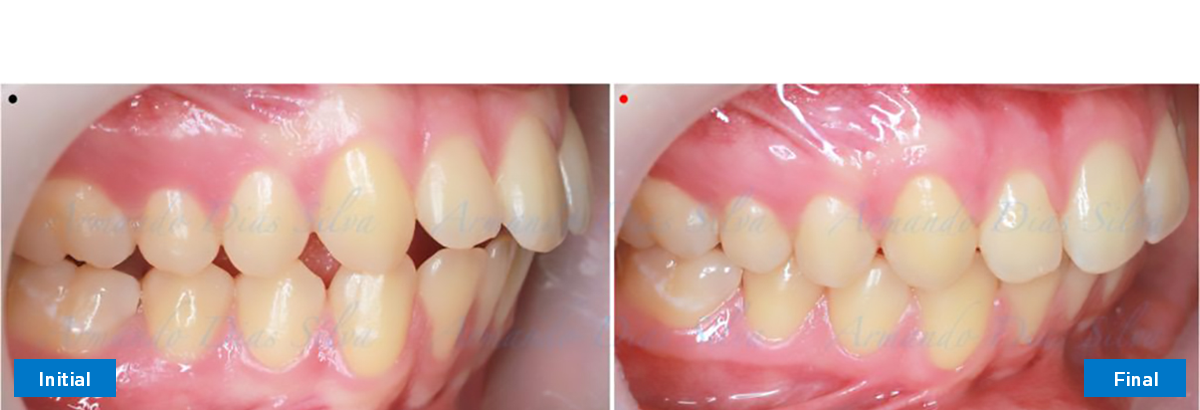

Clase II, Div. 1: Protrusión del incisivo central y espacios anteriores (SureSmile® Aligners)

Principal queja del paciente: Protrusión del incisivo central y mordida abierta. El paciente rechaza la expansión del arco palatino (MARPE) y las extracciones.

Este paciente adolescente presenta molares de Clase II y no le gusta su mordida abierta ni lo protrusivos que son sus dientes frontales. Por sus fotografías faciales, parece que su mandíbula es retrognática o le falta volumen en la barbilla. El historial del paciente también indica que existe un problema funcional al no haber guía de los incisivos.

• Molares de clase I logrados con distalización y sin elásticos

• Sin expansión maxilar, respetando la envoltura periodontal

• Incisivos inferiores retroinclinados, que mejoran la estabilidad a largo plazo

Retención: Arco superior retenido con retenedor transparente. Arco inferior retenido con retenedor lingual unido de canino a canino.